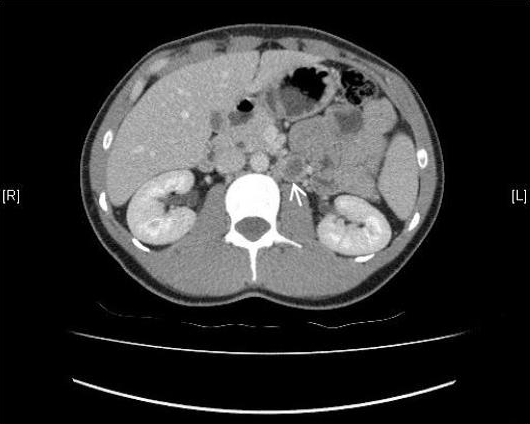

After orchidectomy, computed tomography scan of chest, abdomen, and pelvis with contrast was performed to assess for lymphatic involvement or metastatic spread (Figure 3). Computed tomography (CT) scan showed evidence of left para-aortic lymph node enlargement 22x21 mm with a necrotic centre. A few small volume lymph nodes were also noted adjacent to this enlarged necrotic node. There was no evidence of lung, liver or bony metastasis or lymphadenopathy and bony windows were unremarkable.

Figure 3: Computed tomography scan of chest, abdomen, pelvis with contrast showing an enlarged left para-aortic lymph node of 22x21 mm (arrow) with a necrotic centre and a few adjacent small volume lymph nodes.